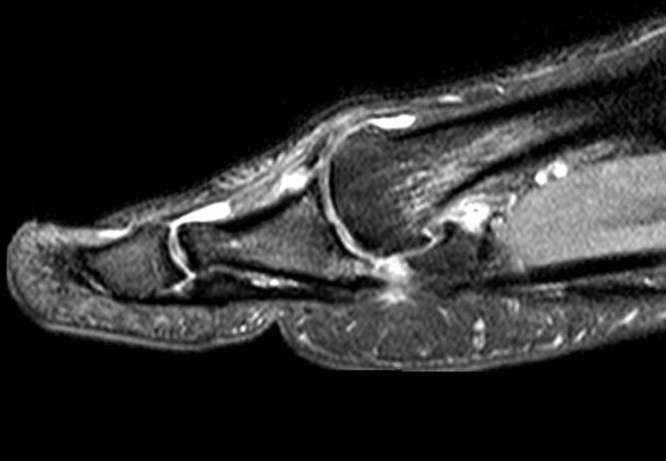

MRI

Sagittal images

Complete plantar plate avulsion